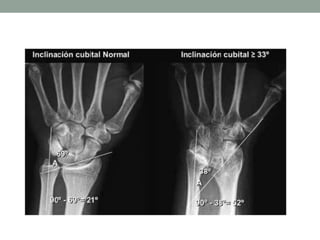

Diagnóstico Imagenológico

• McCarroll et al. 2010

• Tilt ulnar ≥ 33º (90 – A)

• Angulo entre línea de polo proximal de

escafoides y semilunar con respecto al

eje de la ulna

• Subsidencia del semilunar

• Angulo de la fosa semilunar

• Desplazamiento volar del carpo

Diagnóstico Imagenológico • McCarrollet al. 2010 • Tilt ulnar ≥ 33º (90 – A) • Angulo entre línea de polo proximal de escafoides y semilunar con respecto al eje de la ulna • Subsidencia del semilunar • Angulo de la fosa semilunar • Desplazamiento volar del carpo